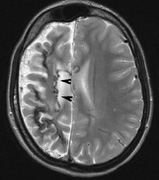

Neurologic Findings INTRACRANIAL LESIONS. Mental retardation and seizures in TSC are often associated with benign CNS astrocytic hamartomas.131 On imaging, the cerebral lesions show three patterns:132

SEIZURES. Typically observed first in infancy, seizures are a common presenting sign of TSC and a frequent source of morbidity. The seizures often begin as “salaam spasms”—repetitive myoclonic spasms that produce head nodding with associated extension/flexion of the trunk and limbs. They often progress to grand mal seizures25,116 and may be difficult to control. Vigabatrin has been advocated for control of infantile spasms but it carries a risk for irreversible visual field loss. Other treatments include corticosteroids, adrenocorticotrophic hormone, and a ketogenic diet.25,137–139 Selective surgical excision of an “epileptogenic tuber” may be an option for intractable epilepsy.140 MENTAL RETARDATION. Mental deficiency, part of Vogt's diagnostic triad (adenoma sebaceum, epilepsy, mental deficiency),3 affects about 50% of patients overall.25,141 TSC2 mutations may carry a higher risk than TSC1.142 AUTISM. This may affect 50% to 60% of TSC patients, possibly correlating with numbers of cerebellar and temporal tubers.25,143,144 Visceral Findings Patients with TSC may have renal, cardiac, pulmonary and other visceral involvement. RENAL. The TSC2 gene was localized by linkage with the polycystic kidney disease gene in patients with TSC and polycystic kidneys. This represents a contiguous gene syndrome in which adjacent genes (PKD1 and TSC2) are deleted together.145–147 Multiple angiomyolipomas of the kidney are benign hamartomas of blood vessels, smooth muscle, and fat. By 10 years of age, the frequency of angiolmyolipomas is 75%, similar to adults.148 The fat signal of angiomyolipomas helps to distinguish them from renal cell carcinoma.25 Renal insufficiency/failure may be the complication of both cystic disease and angiomyolipomas and is one of the leading causes of morbidity and mortality in TSC.138,149 CARDIAC. Rhabdomyoma are usually multiple, typically asymptomatic, and often regress with age.150,151 PULMONARY. Lymphangioleiomyomatosis is a progressive lung disease characterized by bronchiolar smooth muscle infiltration and cystic changes of the lung parenchyma. About 1% of adult females with TSC are affected.116,152,153 OPHTHALMIC FEATURES The principal ophthalmic manifestations of TSC are in the posterior segment. Astrocytic Retinal Hamartomas Although in Van der Hoeve's original description the term phakoma or phakomata was a generic term for the tumors occurring in various organ systems,1 it has become associated with the retinal astrocytic tumors of TSC,3 which occur in about 50% of affected patients and are bilateral in 25% to 30% (Table 3, Fig. 16).154,156

Historically, the presence of mixed (type 3) hamartomas led to the suggestion of evolution from the type 1 to the type 2.157 A long-term photographic study found that although the types remained unchanged, a minority of types 1 and 3 increased in calcification and a new lesion was noted that had not been evident on an earlier photograph.157 All three types of retinal hamartomas may be found in young children. There is no correlation between age and the predominant type of lesion.156 Histologically, phakomata are composed of glial astrocytes—elongated, fibrous astrocytes with small oval nuclei, arising from the retina or the optic disc. The type 2 lesions contain basophilic, calcified drusen-like deposits within a dense vascular network. On fluorescein angiography, the type 2 lesions show autofluorescence, leakage with transit of dye, and marked late hyperflorescence.3,113 Astrocytic retinal hamartomas usually do not affect vision and require no treatment. Vitreous seeding and vitreous hemorrhage have been reported in association with phakomata, but these are rare.158,159 Laser photocoagulation may be considered in rare cases were exudation induces serous retinal detachments.160 The differential diagnosis of “white retinal lesions” includes retinoblastoma, toxoplasmosis and toxocara.3,113 Pigmentary Abnormalities Depigmented “punched-out” chorioretinal lesions in the midperiphery have been reported in up to 40% of patients. Similar lesions may be found in normal patients.156 Nonretinal Features The adnexae may be involved by angiofibromas: eyelid skin and “salmon-colored” subconjunctival nodules. Sector iris depigmentation and iris coloboma have been reported in a minority of patients.113,156,161 DIAGNOSTIC CRITERIA When TSC is classical (“Salaam seizures,” facial angiofibroma, developmental delay), the diagnosis is straightforward. However, children can be mildly affected, and many of the classical signs may become apparent later. Based on the revised clinical diagnostic criteria set forth by the Tuberous Sclerosis Consensus Conference162, a diagnosis of TSC may be made if the patient has two major features, or one major feature plus two minor features. Genetic testing for TSC still has a high false-negative rate (Table 4).25,162,163 TABLE 4. Features of Tuberous Sclerosis Complex